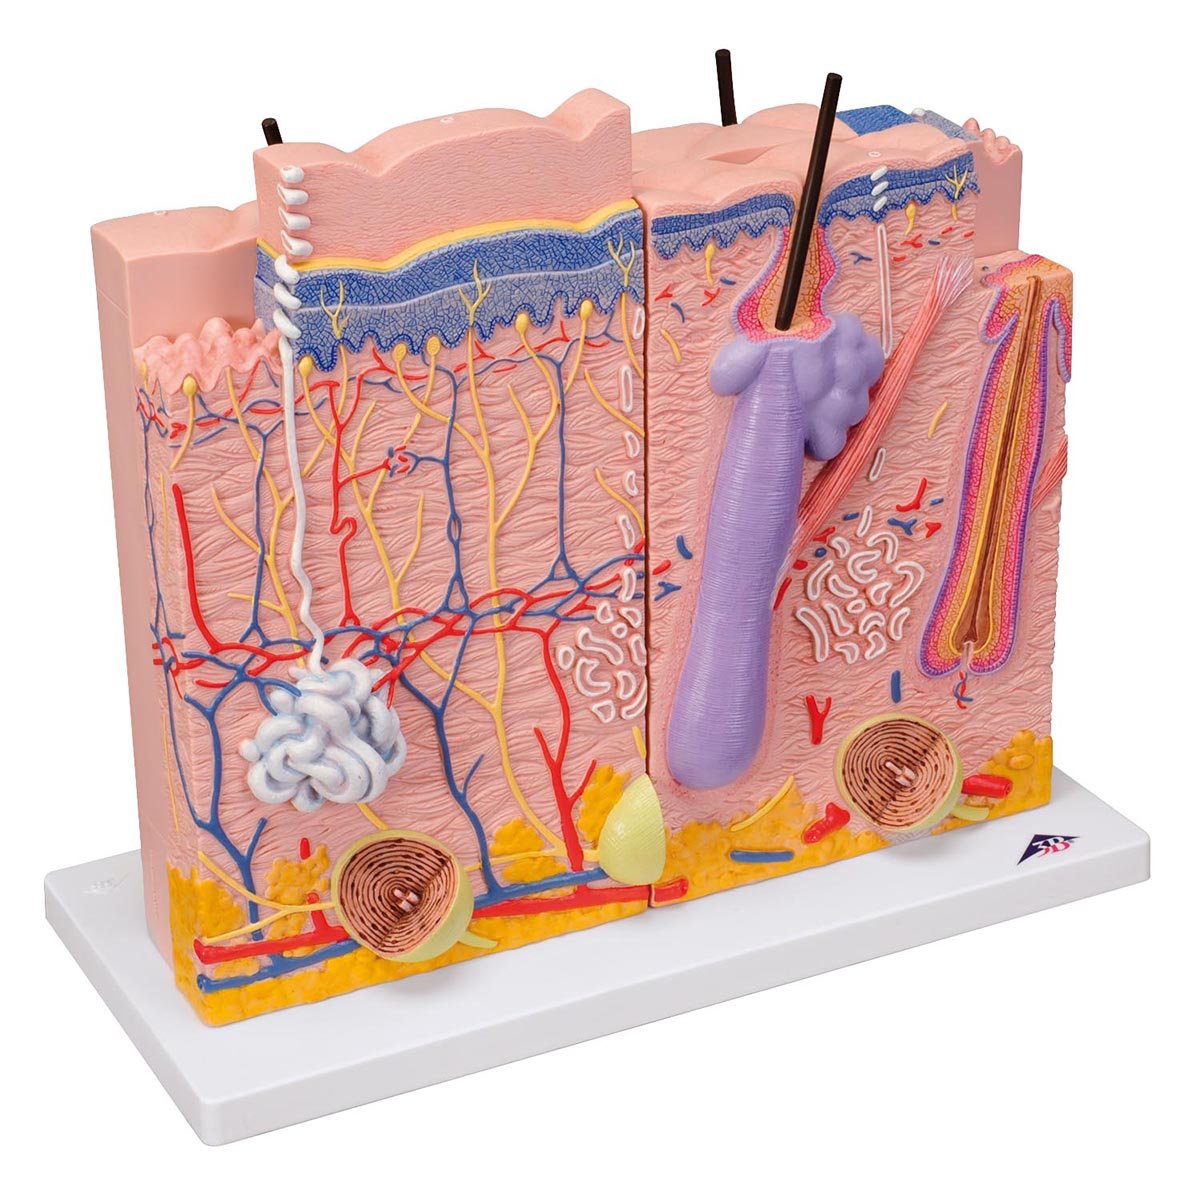

Salg af anatomiske modeller er det bærende element i eAnatomi, selvom vi også bruger mange ressourcer på at udvikle vores egne anatomiske materialer som fx plakater. Anatomiske modeller anvendes til forskellige formål og kan både vise afgrænset væv, organer samt organsystemer. Søger du en simpel model af knoglevæv eller måske en avanceret torso-model baseret på MRI teknologi, kan du finde det hele på eanatomi.com.